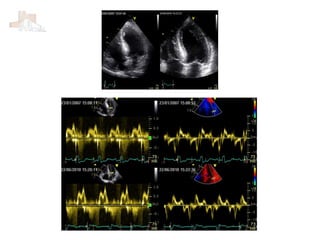

J Am Soc Echocardiogr 2016;29:277-314

Función diastólica J AmSoc Echocardiogr 2016;29:277-314

J Am SocEchocardiogr 2016;29:277-314